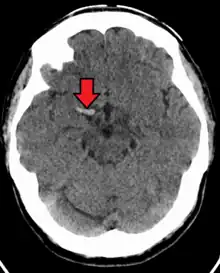

| CT scan without intravenous contrast showing hyperdense aspect of the right middle cerebral artery, indicating thrombus within the vessel | |

In medicine, the dense artery sign or hyperdense artery sign is an increased radiodensity of an artery as seen on computer tomography (CT) scans, and is a radiologic sign of early ischemic stroke.[1] In earlier studies of medical imaging in patients with strokes, it was the earliest sign of ischemic stroke in a significant minority of cases.[2] Its appearance portends a poor prognosis for the patient.[3][4]

The sign has been observed in the middle cerebral artery (MCA),[4] posterior cerebral artery (PCA),[5] vertebral artery,[2] and basilar artery;[6] these have been called the dense MCA sign, dense PCA sign, dense vertebral artery sign, and dense basilar artery sign, respectively.

Through cerebral angiography, the sign has been demonstrated to correspond to embolic or atherosclerotic occlusion of an artery.[1] Specifically, the hyperdensity is thought to be due to calcification or hemorrhage associated with an atherosclerotic plaque.[1]

Identification of the dense artery sign is often based on subjective interpretation and false positives may occur. One study aiming to define criteria for the sign determined that measuring Hounsfield units on the CT scan could differentiate between the dense MCA sign associated with ischemic stroke and that caused by false positives.[8] Specifically, the combination of greater than 43 Hounsfield units and an MCA density ratio of greater than 1.2 was diagnostic of a dense MCA sign associated with acute ischemic stroke.[8]